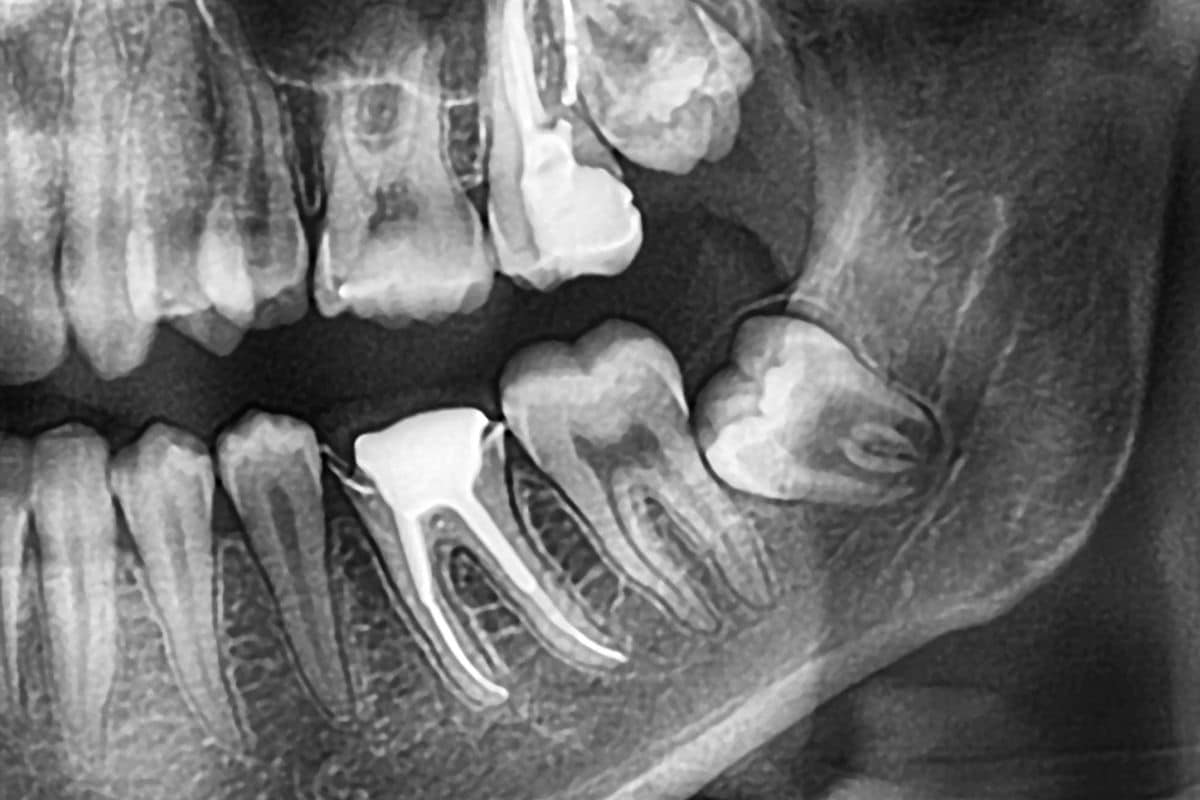

Impacted Wisdom Teeth and Oral Hygiene

Moreover, impacted wisdom teeth can push against other teeth, creating gaps and spaces that make it challenging to maintain proper oral hygiene.